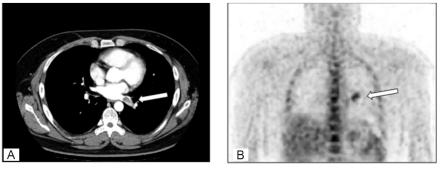

Extension of metastatic lung tumors into the left atrium via pulmonary veins is rare. Here, we report the first case of Ewing sarcoma exhibiting such extension. A 31-year-old man with pulmonary metastasis from Ewing sarcoma presented with a mass in the left lung, extending to the left atrium through the left inferior pulmonary vein. As the patient was considered to be at risk of tumor embolism, the mass was excised surgically.

转移性肺肿瘤经肺静脉延伸至左心房的情况较为罕见。在此,我们报告首例出现这种延伸情况的尤因肉瘤病例。一名31岁的男性,患有尤因肉瘤肺转移,表现为左肺有一肿块,经左下肺静脉延伸至左心房。由于该患者被认为有肿瘤栓塞风险,遂通过手术切除了肿块。